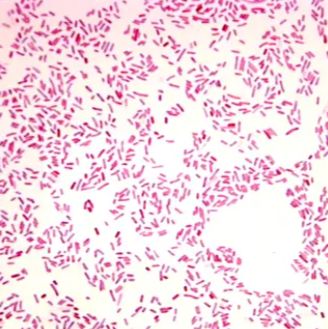

快速革兰氏染色(实验检测)

快速革兰氏染色(实验检测) 革兰氏染色,革兰氏染色法可用来观察细菌的形态并鉴别细菌;在选择药物方面有一定的参考价值;革兰氏阳性菌能产生外毒素,革兰氏阴性菌能产生内毒素,两者的致病作用不同,与致病性也有关。革兰氏阳性菌呈蓝色或蓝紫色,革兰氏阴性菌呈红色。 革兰氏染色是一种常用的细菌鉴

文献支持服务名称:快速革兰氏染色(实验检测)提供商:上海信帆生物